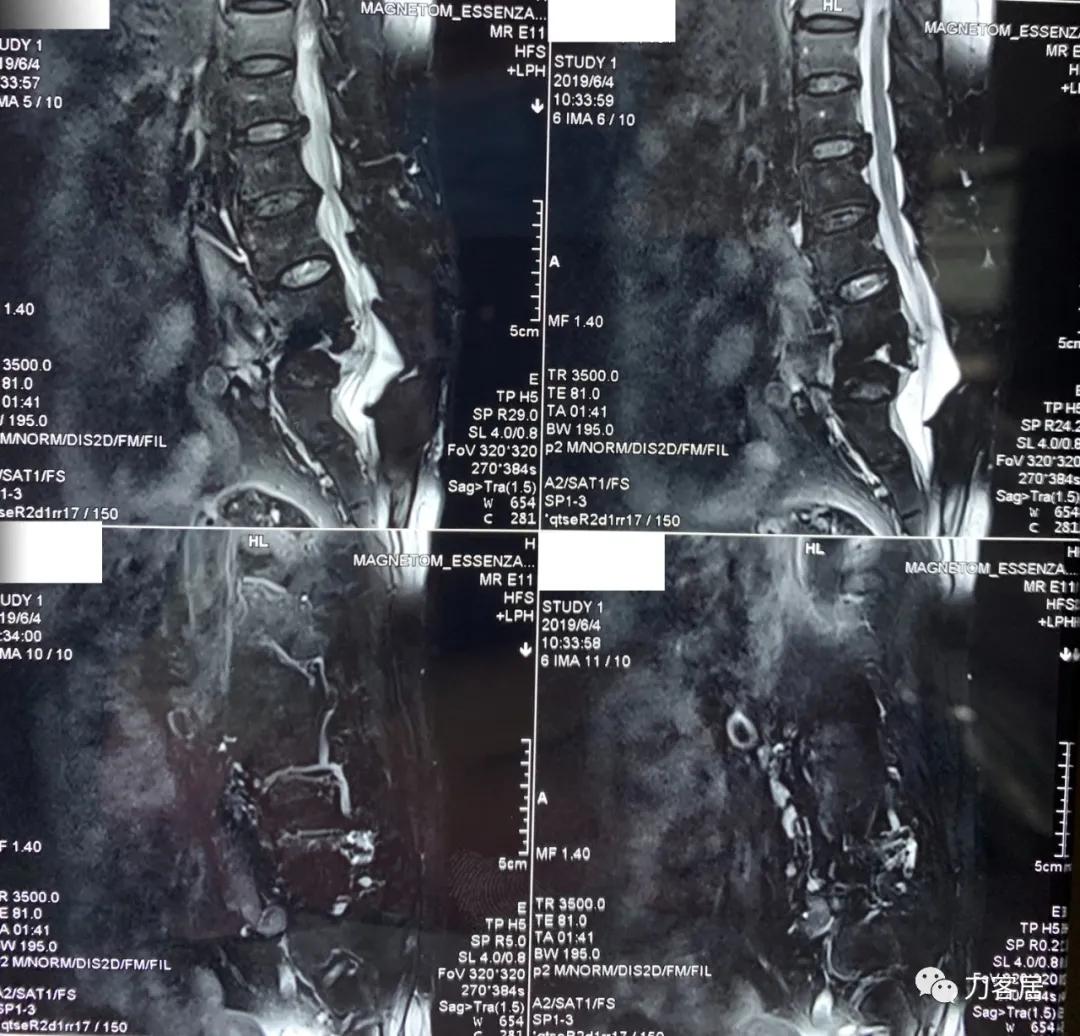

家属携带的影像学检查提示腰4-骶1病灶清除植骨融合术后改变,骨质疏松严重,未见椎旁脓肿以及结核病灶复发破坏。血沉、C反应蛋白化验检查结果正常。

诊断:腰4-骶1病灶清除植骨融合术后,严重骨质疏松症。

图5. 20190604腰椎MRI02

图6. 20190604腰椎MRI01

图7. 20190604腰椎MRI03

图8. 20190604腰椎MRI04